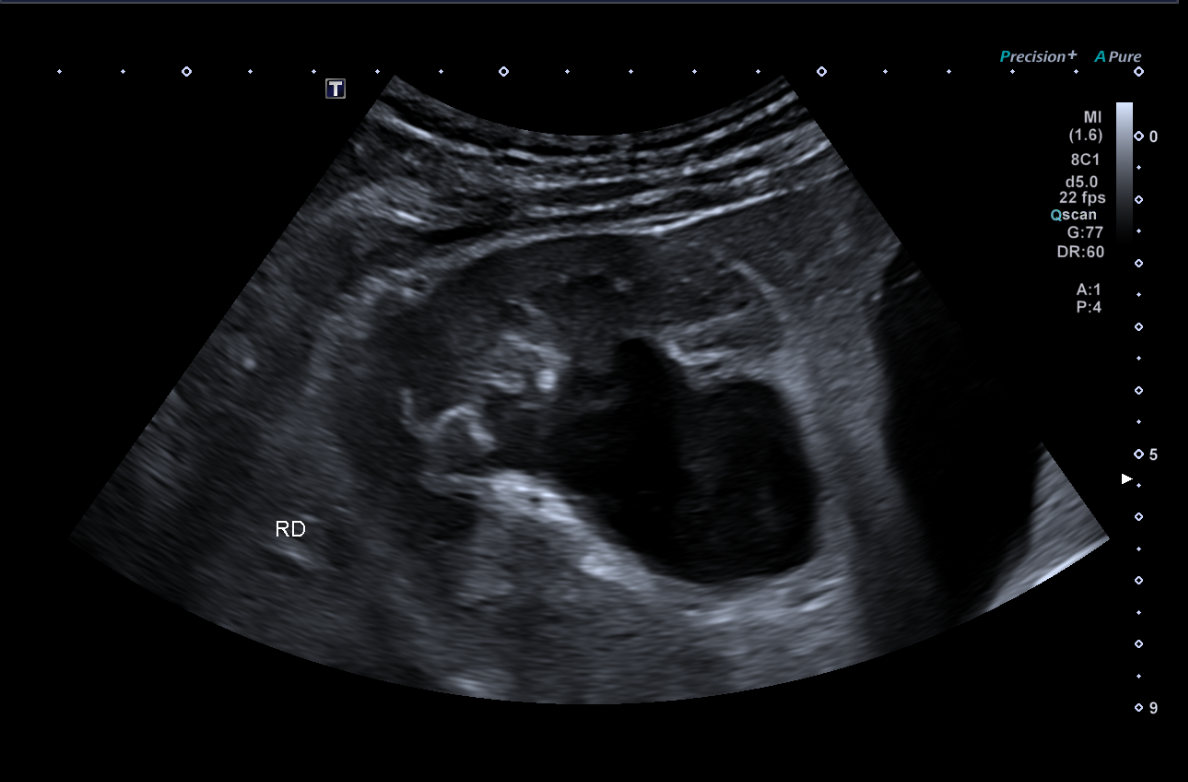

Se establece como hipótesis diagnóstica hidronefrosis. Se plantea como diagnóstico diferencial posible cistitis ulcerativa, así como uropatía obstructiva secundaria a consumo de ketamina. La ecografía clínica resulta determinante para la confirmación diagnóstica, evidenciando datos compatibles con obstrucción de la vía urinaria.

En vista del deterioro de la función renal del paciente, se decide ingreso hospitalario en medicina interna. Se realiza ecografía renal reglada por radiología la mañana siguiente, encontrando hidronefrosis grado III-IV bilateral.